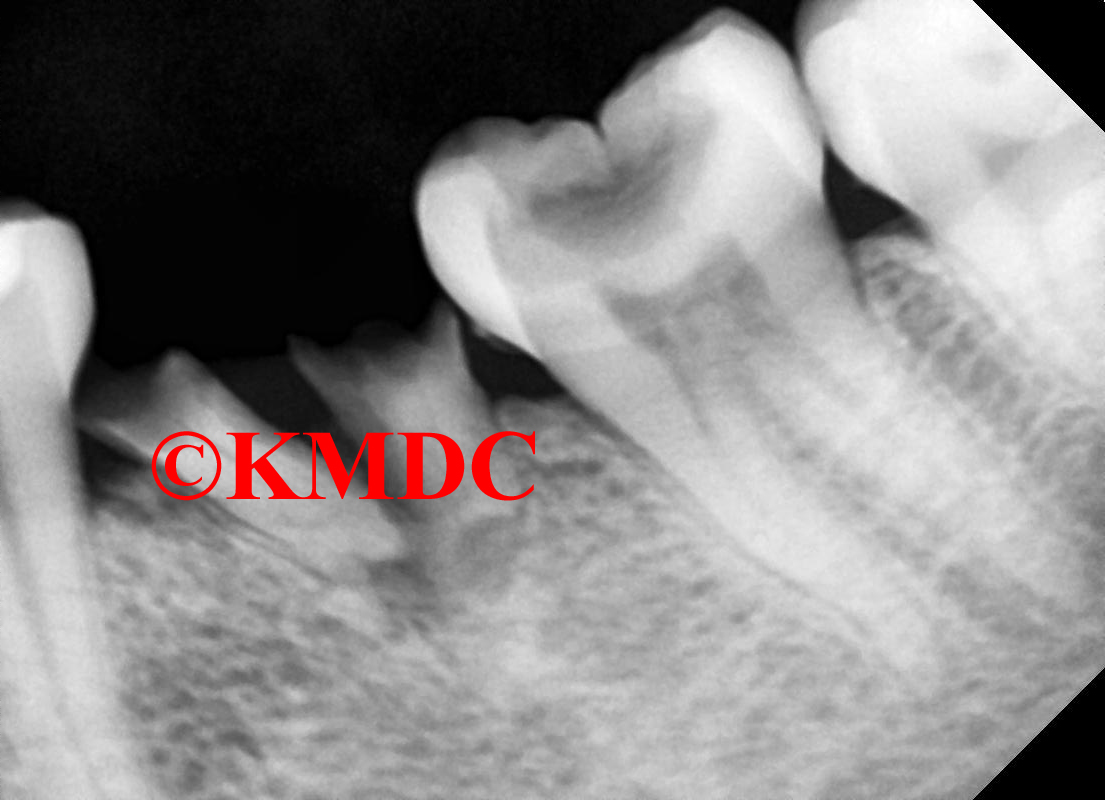

Clinical Gallery